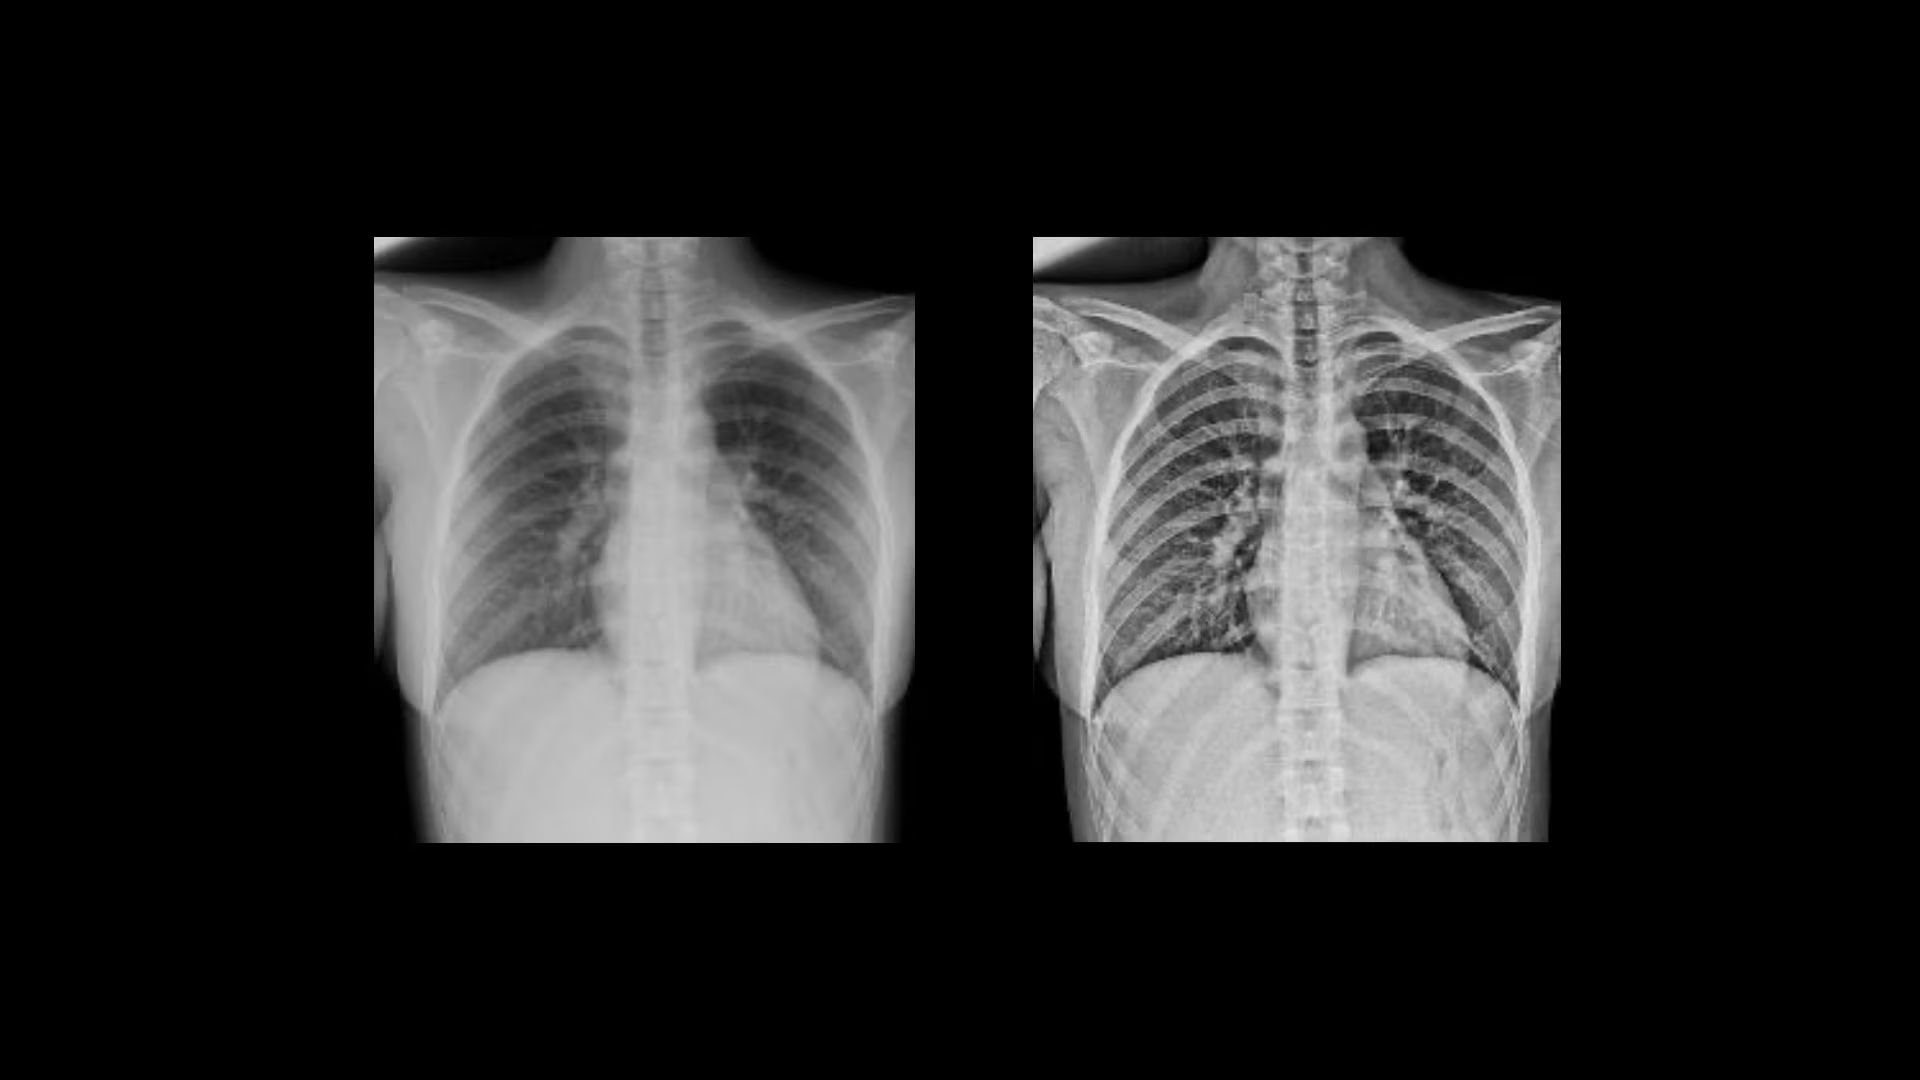

Consistency

Harness AI for improved consistency

Automated AI Brightness and Contrast (AIBC)

delivers consistent brightness and contrast for 56* anatomy and view combinations regardless of variations in dose, patient positioning, field of view and metal implants. By automatically adjusting brightness and contrast to a user-defined preference, Helix's AIBC can help reduce technologist image processing time by up to 87%.¹

web-helix-feature-ci-en